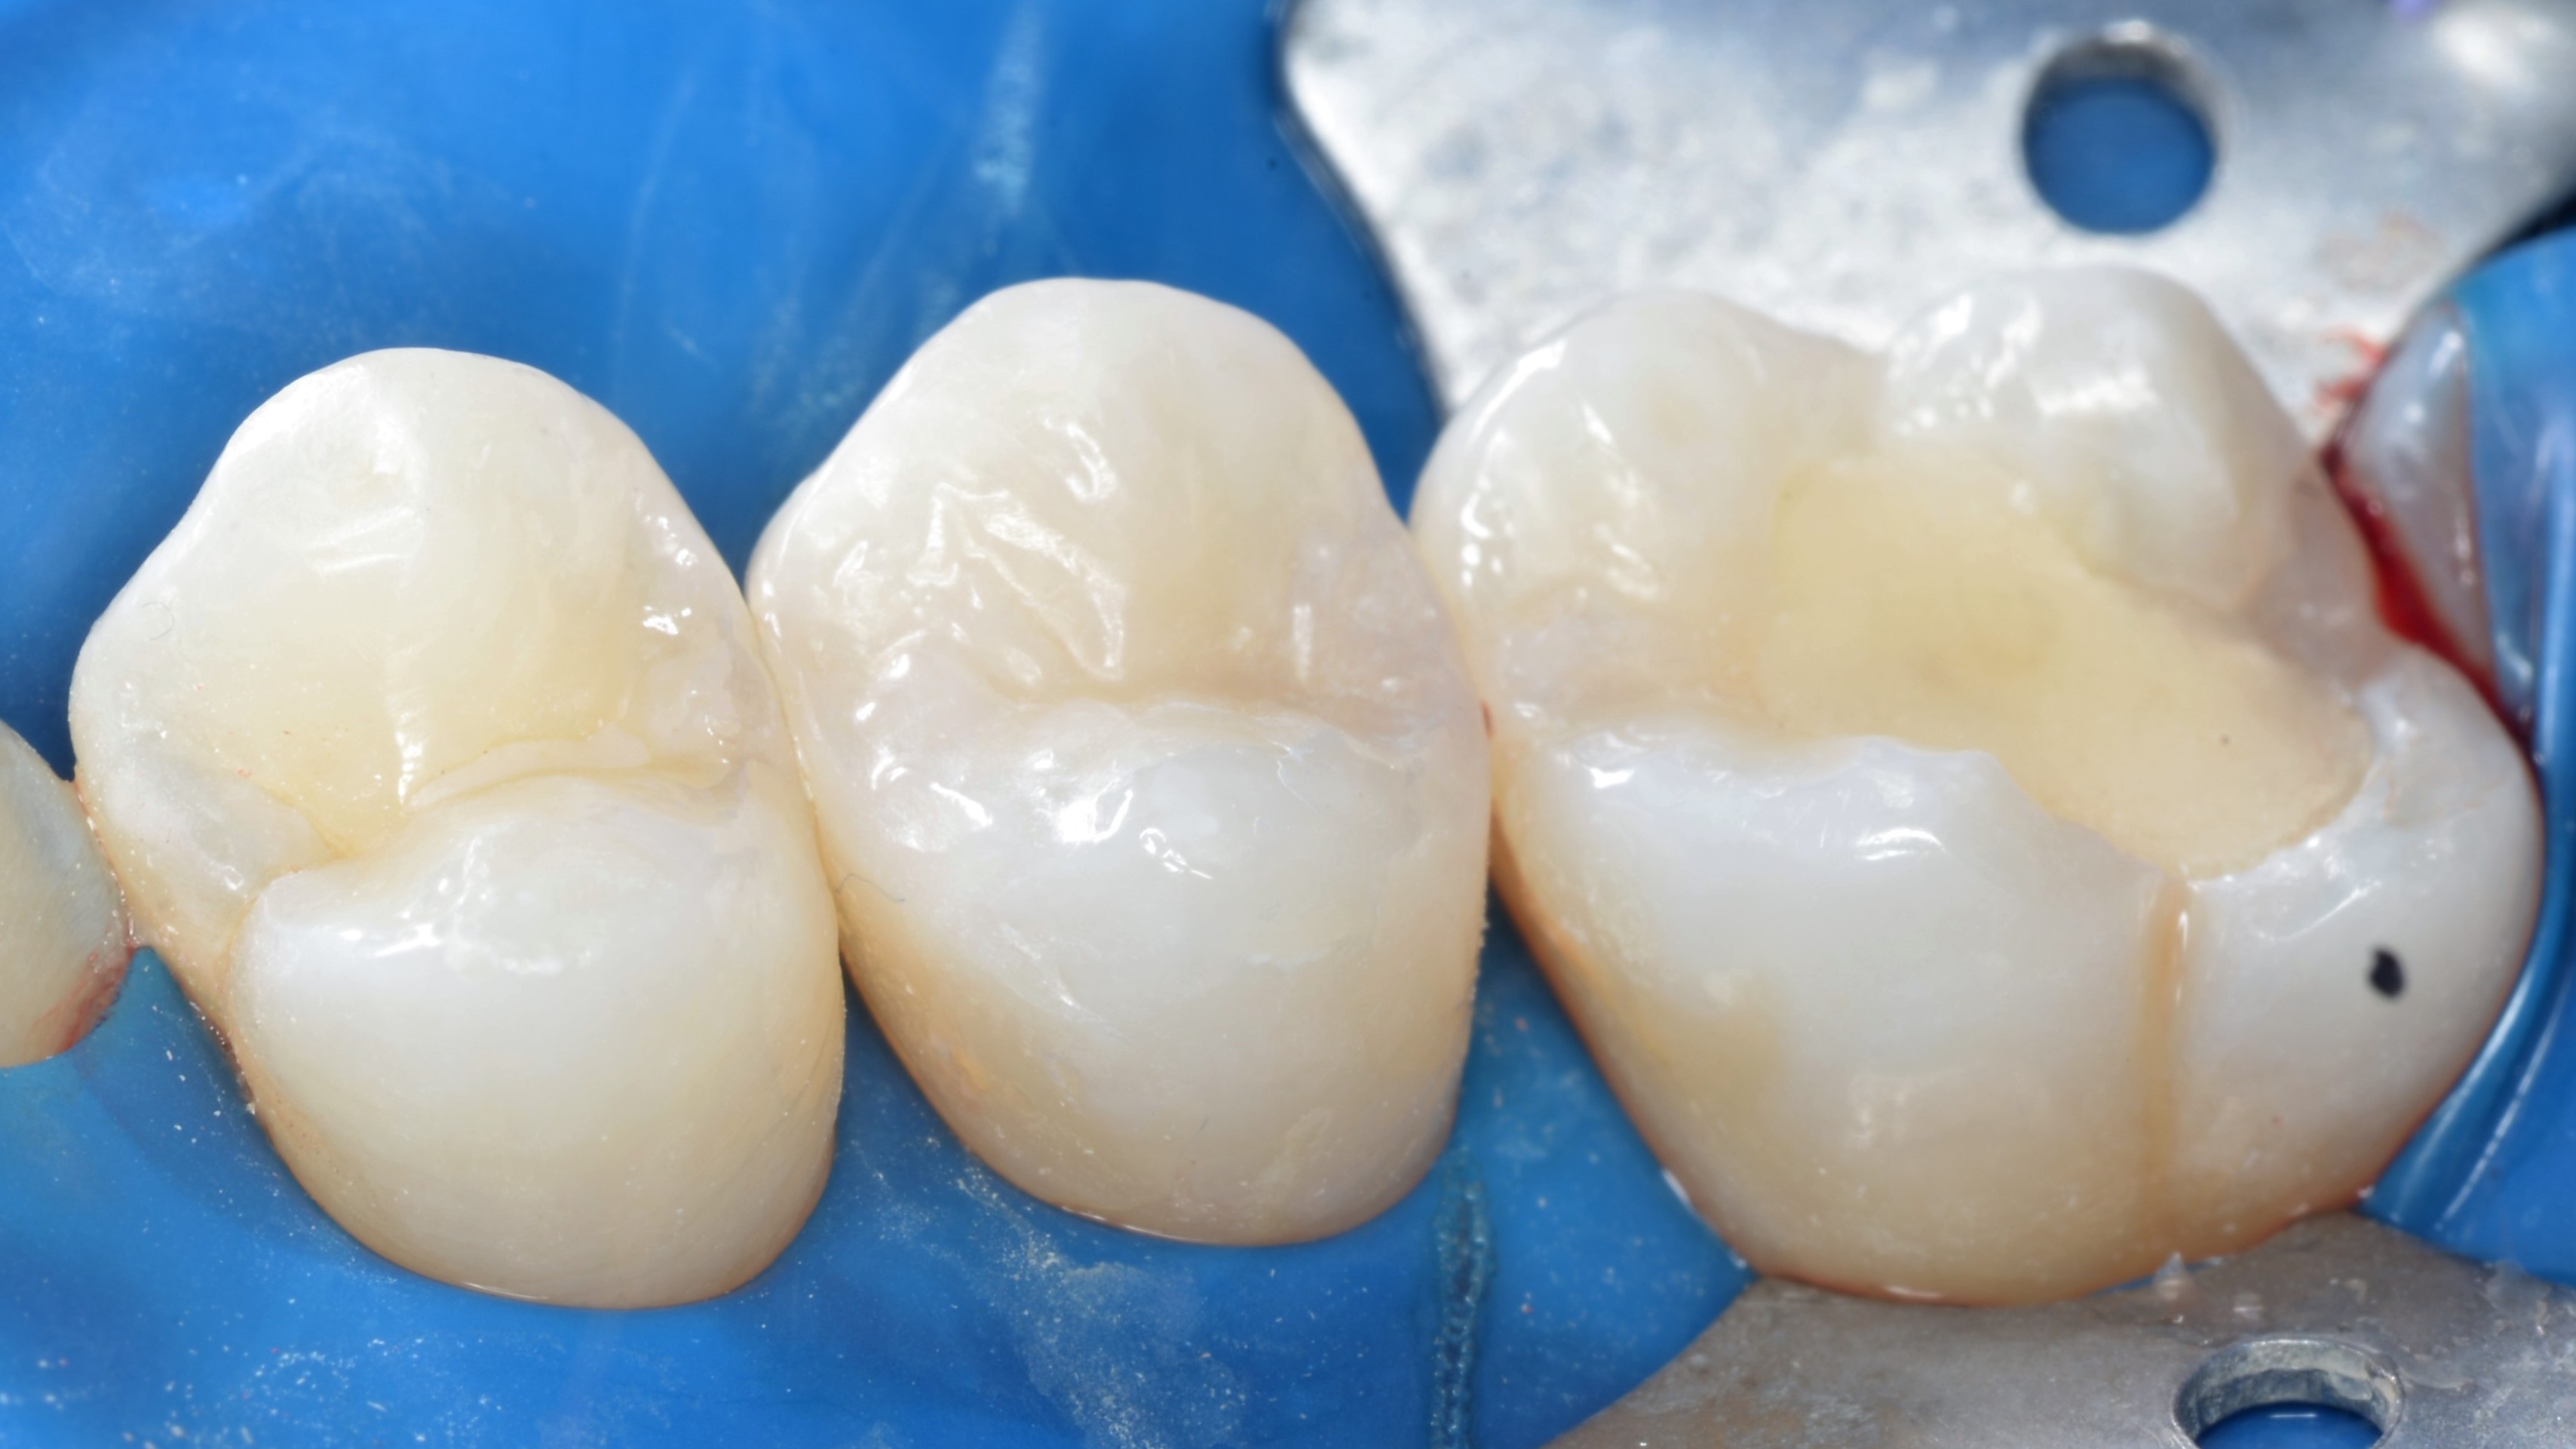

Wypełnienia wykończono dyskami ściernymi z nasypem z tlenku glinu (Sof-lex, 3M) oraz gumką impregnowaną węglikiem krzemu (BAL109F "brownie", Nevadent). Wstępne polerowanie wykonano gumkami diamentowymi Clearfil Twist DIA (Kuraray Noritake) oraz szczoteczkami nylonowymi (ryc. 9, 10). Odbudowy dostosowano w zgryzie i ostatecznie wypolerowano (ryc. 11, 12).

Ryc. 9. Wykończenie wypełnień (Sof-lex, 3M, BAL109F "brownie", Nevadent) i polerowanie wstępne (Clearfil Twist DIA, Kuraray Noritake, szczotka nylonowa).

Ryc. 10. Wykończenie wypełnień (Sof-lex, 3M, BAL109F "brownie", Nevadent) i polerowanie wstępne (Clearfil Twist DIA, Kuraray Noritake, szczotka nylonowa).

Ryc. 11. Stan po korekcie w okluzji i polerowaniu ostatecznym (Clearfil Twist DIA, Kuraray Noritake, szczotka nylonowa).

Ryc. 12. Stan po korekcie w okluzji i polerowaniu ostatecznym (Clearfil Twist DIA, Kuraray Noritake, szczotka nylonowa).